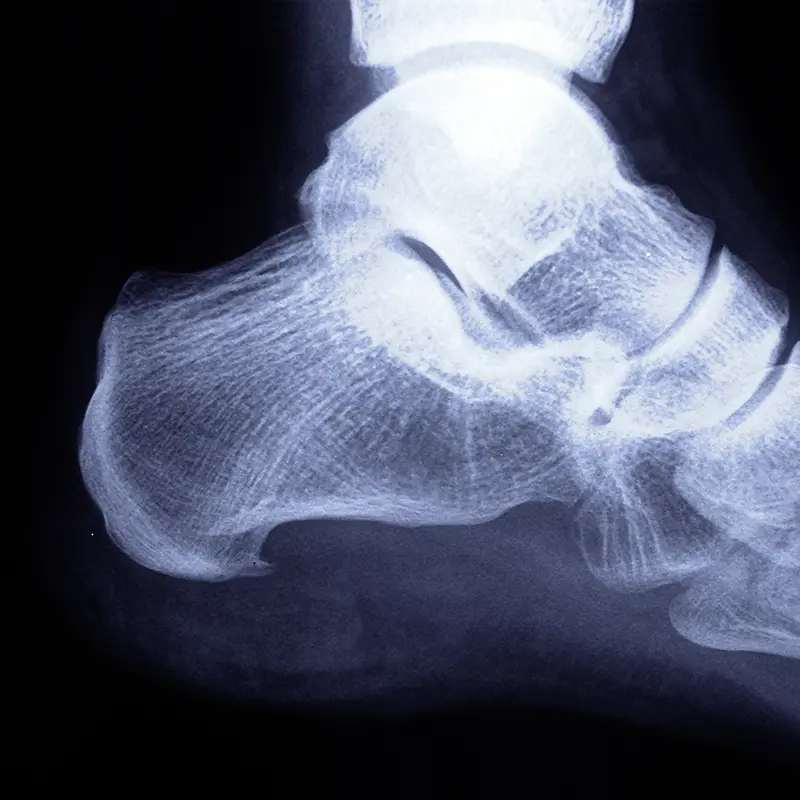

Las patologías que afectan a estas zonas del pie suelen tener un componente biomecánico importante y, en muchos casos, una evolución prolongada en el tiempo.

Engloban problemas como:

- Fascitis plantar, cuando no responde a tratamientos conservadores.

- Atrapamientos nerviosos (túnel del tarso, neuropatía de Baxter).

- Tendinopatías (tibial posterior, tendón de Aquiles, tendones peroneos).

- Cirugías del retropié (pie plano, artrosis, huesos accesorios).

- Cirugía reconstructiva (tratamiento de deformidades complejas y secuelas de lesiones en el pie y tobillo).

En estos casos, la indicación quirúrgica se valora de forma individual, teniendo en cuenta la biomecánica del pie y el impacto real del problema en la vida diaria.